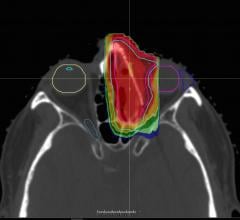

Proton therapy, or proton beam therapy, is a type of radiation therapy used to treat cancer. At a high energy, the positively charged particles can destroy cancer cells.